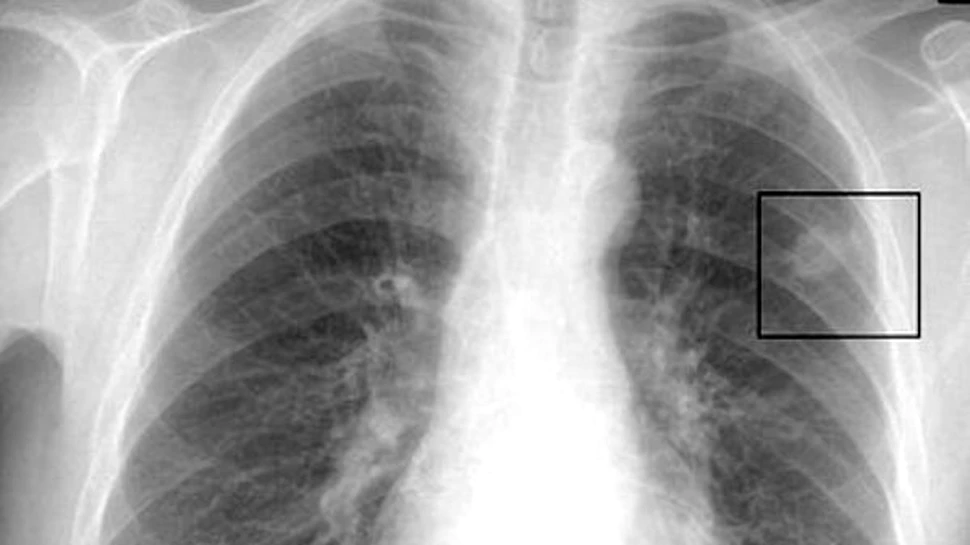

Cele mai frecvente tipuri de cancere dignosticate in 2008 au

fost, in ordine: cel pulmonar, cancerul de san si cancerele colorectale.

Cele mai multe decese s-au produs din cauza cancerului la

plamani, la stomac si la ficat.